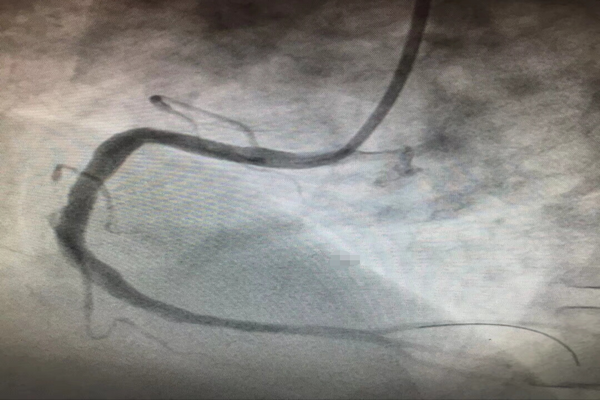

——熱烈祝賀我科成功完成西北首例Resolute Integrity冠脈支架植入術(shù)

10月16日,入秋的夜晚已是寒冷刺骨,但在介入室內(nèi)我們心內(nèi)科的手術(shù)卻做的是熱火朝天。大家在徐曉輝主任的帶領(lǐng)下連續(xù)奮戰(zhàn)至凌晨2點半,雖然身感疲憊、汗流浹背,但是大家的內(nèi)心卻是無比激動的,因為我們?yōu)獒t(yī)院、為我們心內(nèi)科創(chuàng)造了一個“西北第一”,即“首例Resolute Integrity冠脈支架植入術(shù)”,為西北地區(qū)第一例在術(shù)中應(yīng)用該支架的病例。

運用最新的正弦波技術(shù)制作而成的Resolute Integrity冠脈支架擁有更好的通過性及順應(yīng)性,不僅確保了支架能夠順利通過更加迂曲、成角的病變,而且更加確保了支架植入在大于直徑4.0mm的冠脈內(nèi)能夠貼壁良好,從而保證了在冠脈恢復(fù)TIMI3級血流的基礎(chǔ)上減少術(shù)后急、慢性血栓的發(fā)生。

但是,光有支架還不行,還必須要有能夠駕馭它的人。而此次手術(shù)的患者,不僅僅是病變血管直徑較一般人粗,而且病變部位嚴重成角、迂曲,支架植入手術(shù)是非常困難的。擁有工匠精神的徐曉輝主任不畏困難、勇于挑戰(zhàn),在近20年介入手術(shù)經(jīng)驗的基礎(chǔ)上,運用嫻熟的操作技巧,厚積薄發(fā),成功地完成了我院首例5.0mm直徑冠脈支架植入手術(shù),術(shù)后效果堪稱完美!